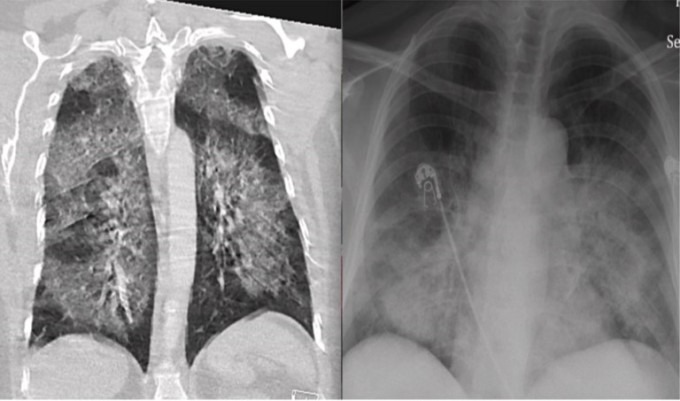

Triệu chứng của EVALI xuất hiện hàng giờ, hàng tuần trước khi nhập viện, gồm khó thở, ho, đau ngực, tiêu chảy, đau bụng, sốt, mệt. Sau đó, các chỉ số như máu lắng, bạch cầu đều tăng, ảnh chụp X-quang cho thấy phổi tổn thương trông lỗ chỗ như bánh mì hoặc như bỏng ngô.